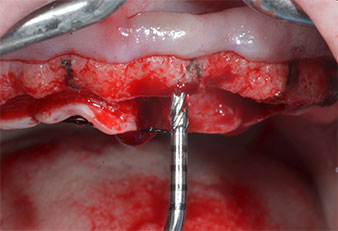

Para marcar las posiciones del implante y realizar la preparación piloto, se utilizó un inserto piezoeléctrico (Piezomed I1) con revestimiento de diamante y forma de llama (figura 3). Se tomaron precauciones para realizar movimientos hacia arriba y hacia abajo, con una potencia reducida, una irrigación completa y una baja presión (por debajo de 300 g). A continuación, se aplicó un inserto piloto (Piezomed I2A/I2P) para aumentar el diámetro inicial de 2 mm de los sitios de implante (figura 4), seguido de un inserto de 3 mm (Fig. 5).

Fig. 5: El diámetro final se logró con los insertos Piezomed I3A/I3P. En el caso de los implantes de 10 mm de las posiciones 11 y 21, los sitios se finalizaron con una fresa rotatoria de 3,5 mm en un motor de implantes (Implantmed).

Fig. 4: El siguiente paso fue el aumento piloto con los insertos I2A/I2P, que se aplicaron con un movimiento rotatorio horizontal.

Debido al hueso relativamente duro (D2) existente en el sector anterior, los sitios de los implantes largos de 10 mm de las posiciones 11 y 21 se finalizaron con una fresa rotatoria de 4 mm de diámetro, en combinación con un contra-ángulo quirúrgico WS-75 L de W&H, el motor de implantes Implantmed de W&H y el módulo opcional Osstell ISQ de W&H. En cambio, debido a la existencia de hueso blando, los sitios posteriores se prepararon hasta un diámetro final de 3 mm utilizando el inserto Piezomed I3P. Por último, los implantes se colocaron a nivel crestal para su osteointegración durante tres meses (figuras 6-10). La prótesis existente se mantuvo sobre cuatro implantes provisionales (figura 8).